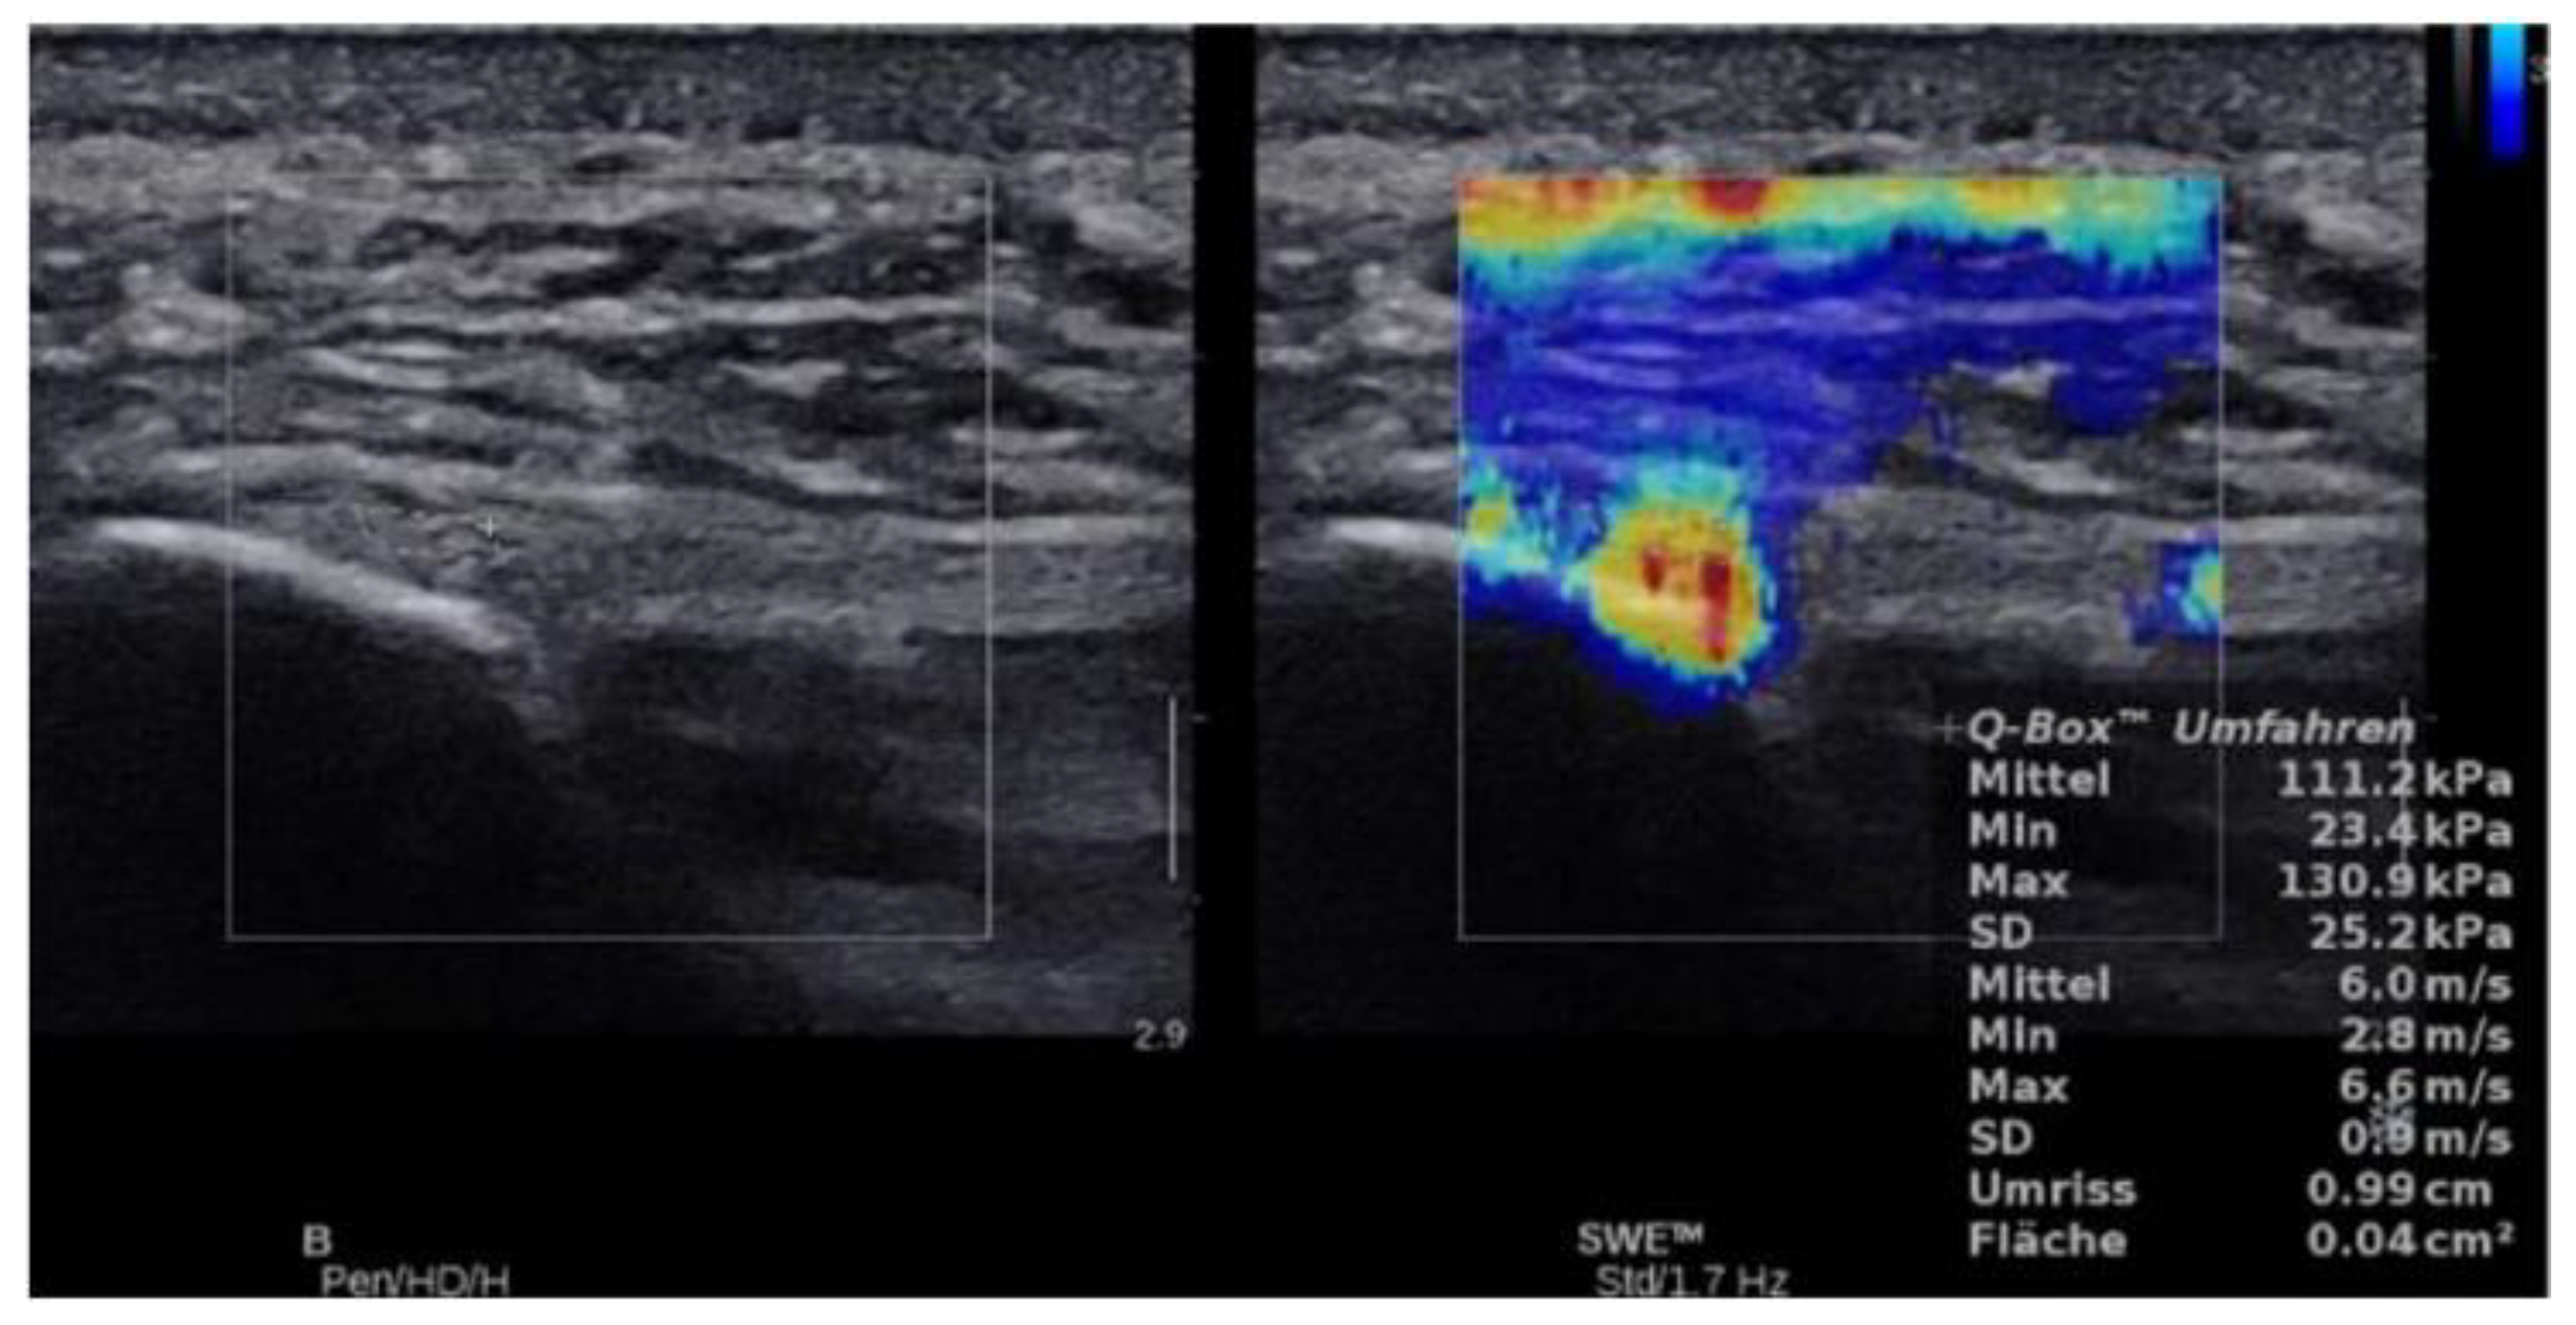

2.4.3. SWE Examination

3. Results